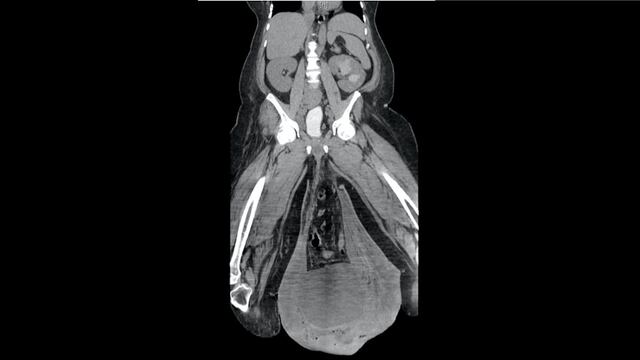

Un paciente de 43 años acudió a un hospital de su localidad en Panamá con síntomas de infección como taquicardia, inflamación y fiebre, además de n gran bulto entre las piernas que de inmediato comenzó a ser analizado por el personal médico que recibió el caso y que al encontrar un escroto tan grande que llegaba a las rodillas del portador, aseguraron no haber visto nada igual antes.

El diagnóstico inicial para el adolorido paciente fue linfedema crónico masivo del escroto, un bloqueo en el sistema linfático que impedía al líquido linfático drenarse y causó la inflamación y acumulación de fluidos; posteriormente, los médico encontraron que también tenía gangrena de Fournier, una infección que puede ser mortal.

Los médico tuvieron que operar de emergencia para retirar la piel y el tejido podrido e infectado. El procedimiento fue un éxito a pesar de que la tarea no fue sencilla, entre otras cosas, porque el pene estaba “enterrado”.